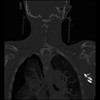

23 ANGIO,CE,Cor-MIP,5.000,ANGIO,Cor-MIP,